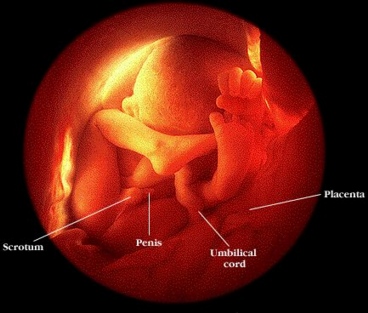

A foto acima descrita, corresponde a uma intervenção

cirúrgica para espinha bífida, realizada dentro do útero

materno num feto de apenas 21 semanas de gestação, numa autêntica

proeza médica, no momento em que o bebé tirou a sua mão

pequena do interior do útero da mãe, tentando segurar um dos

dedos do médico que o operava. Esta mão pequena que comoveu o

mundo pertence a Samuel Alexander, nascido em 28 de Dezembro 1999 (no dia da

foto ele tinha 3 meses de gestação). Quando pensamos bem nisto,

a foto é ainda mais eloquente. A vida do bebé está literalmente

por um fio; os especialistas sabiam que não conseguiriam mantê-lo

vivo fora do útero materno e que deveriam tratá-lo lá dentro,

corrigir a anomalia fatal e fechá-lo para que o bebé continuasse

seu crescimento normalmente.

A história por trás da imagem reflecte a luta e a experiência

passadas por um casal que decidiu esgotar todas as possibilidades, até o último

recurso, para salvar a vida do seu primeiro filho. Essa é a odisseia

de Julie e Alex Arms, que moram na Geórgia, Estados Unidos. Eles lutaram

durante muito tempo para ter um bebé. Julie, enfermeira de 27 anos de

idade, sofreu dois abortos antes de ficar grávida do pequeno Samuel.

Porém, quando, completou 14 semanas de gestação, começou

a sofrer cãibras fortes, e um teste de ultra-som mostrou as razões.

Quando foi revelada a forma do cérebro e a posição do

bebé no útero, o teste comprovou problemas sérios. O cérebro

de Samuel estava mal-formado e a espinha dorsal também mostrou anomalias.

De acordo com Alex, 28 anos, engenheiro aeronáutico, eles sentiram-se

destruídos pelas notícias, mas o aborto nunca seria uma opção.

Em vez de se deixar ir abaixo, o casal decidiu procurar uma solução

pelos seus próprios meios e foi então que ambos começaram

a procurar ajuda. A mãe de Julie encontrou a notícia dos detalhes

de uma cirurgia fetal experimental, desenvolvida por uma equipa da Universidade

de Vanderbilt. Deste modo, entraram em contacto com o Dr. Joseph Bruner (cujo

dedo Samuel segura na foto) e começou uma corrida contra o tempo.

Uma espinha dorsal bífida pode levar a danos cerebrais, gerar paralisias

diversas e até mesmo uma incapacidade total. Porém, quando pode

ser corrigido antes de o bebe nascer, muitas são as chances de cura.

Apesar do grande risco por o bebe não poder nascer ainda naquele momento,

os Arms decidiram recomendá-lo a Deus. A operação foi

um sucesso. Nela, os médicos puderam tratar o bebé, cujo tamanho

não era maior do que o de um porquinho da índia - sem o tirar

do útero, fechar a abertura originada pela deformação

e proteger a coluna vertebral de modo a que os sinais vitais nervosos pudessem

ir agora para o cérebro. Samuel tornou-se o paciente mais jovem que

foi submetido a esse tipo de intervenção.